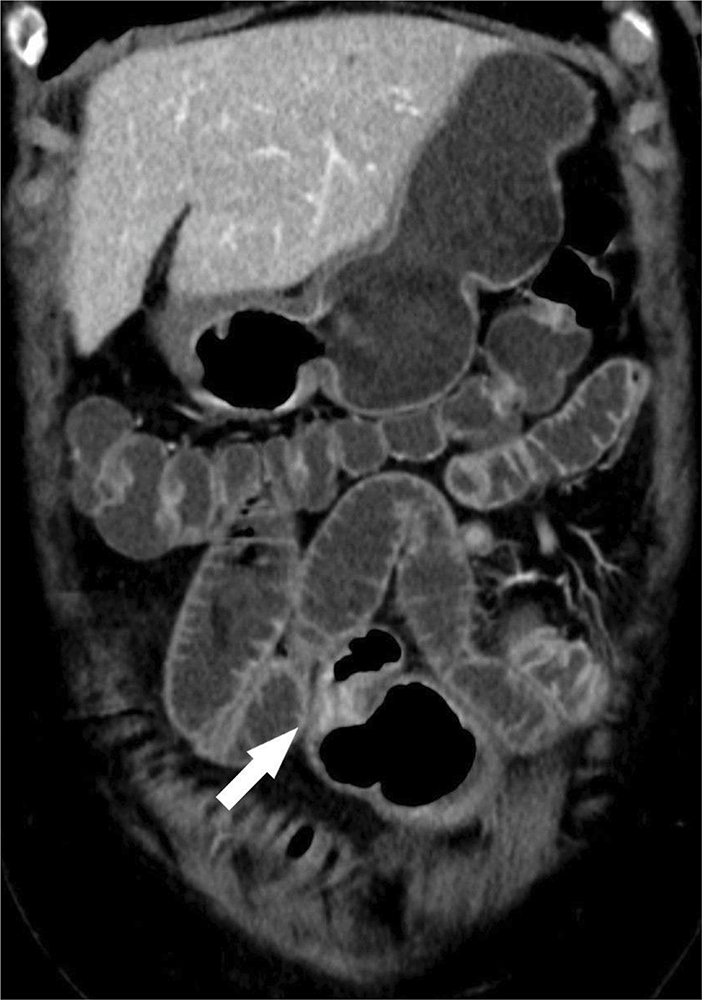

Figure 1b

CT showing stenotic ileal loop with marked contrast‑enhancing wall thickening.